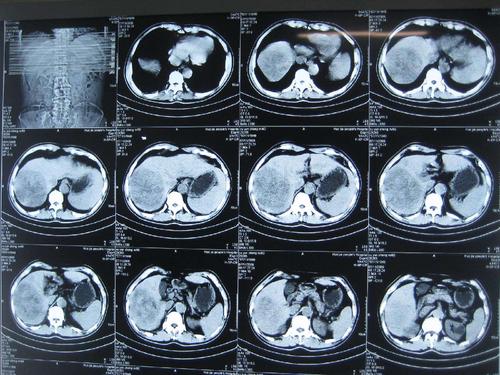

检查结果出来,发现肝内实质性占位,肿瘤达10CM,经过综合评估其他化验指标,确诊肝癌晚期。患者及家属情绪都有些崩溃,后悔不已,“我还不想死,大夫还有办法吗?当时真该切了那个小瘤!”

患者是山东潍坊人,有乙肝病史15年,每次复查肝功能一直正常,也没有接受过任何治疗,渐渐淡忘了这个事。去年做复查发现病毒量7次方,B超显示一个3.5CM的肿瘤--小肝癌。